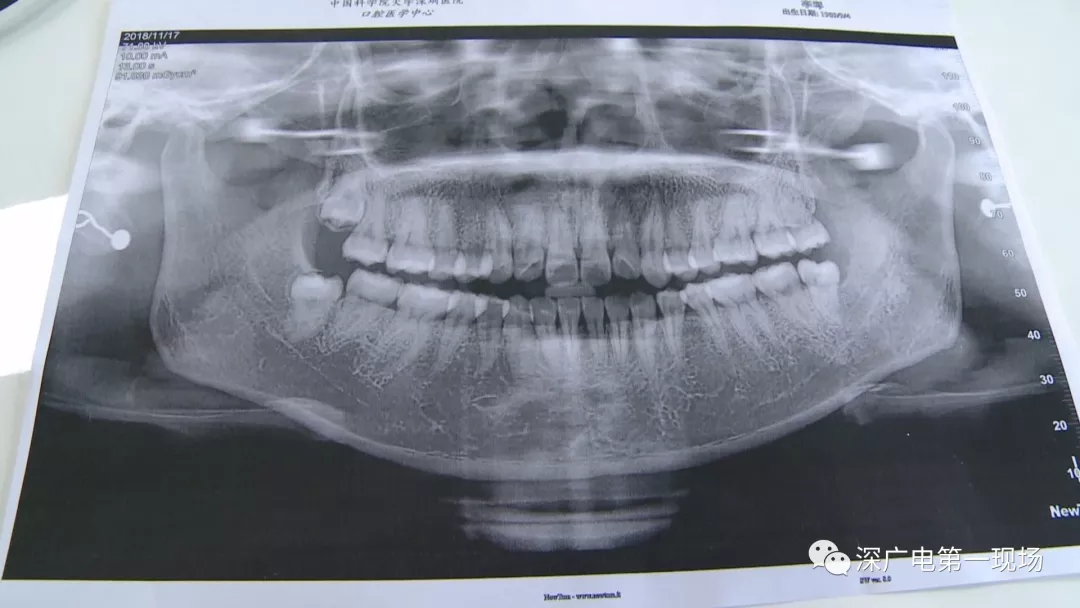

拔一顆智齒一千六?! 深圳這位女士默默的放下了賬單……

隨后,李女士在網(wǎng)上查詢,發(fā)現(xiàn)拔智齒的收費(fèi)都是參差不齊,也沒有參考標(biāo)準(zhǔn)。在李女士提供的拔牙收費(fèi)單上,記者注意到,除了一些拔牙必用的藥物外,還有一些輔助工具的費(fèi)用。

中國(guó)科學(xué)院大學(xué)深圳醫(yī)院口腔科主任賈岳介紹,對(duì)于不同患者的牙齒,它的治療方法都不一樣,所以不同牙齒,醫(yī)院收費(fèi)的標(biāo)準(zhǔn)也各不相同。牙齒的治療方案,都是根據(jù)患者牙齒具體情況來(lái)制定,然后再去收費(fèi),同時(shí)也會(huì)參考病人實(shí)際情況來(lái)做不同的治療項(xiàng)目。